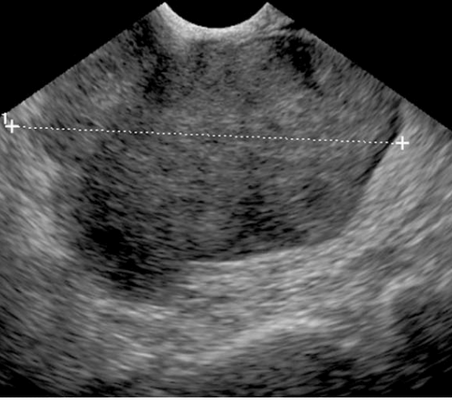

Паровариальная киста составляет 10-20% всех образований яичников. Они происходят из мезосальпинкса- верхнего свободного края широкой связки фаллопиевой трубы. Обычно они односторонние и имеют средний размер около 8 см. При УЗИ они типично гипоэхогенные, округлые или овальные и отделяются от яичника. Содержимое редко бывает с включениями, наличие мягкотканного компонента сразу настораживает в плане опухоли. При КТ паровариальная киста четко очерченное однородное образование, отделяемое от яичника. МРТ малого таза показывает те же признаки, из которых важно, что киста не связана с яичником.

МРТ малого таза. Т2-взвешенная аксиальная МРТ. Параовариальная киста (стрелка).